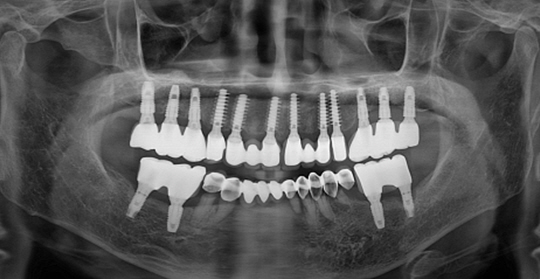

(66세 여 환자)